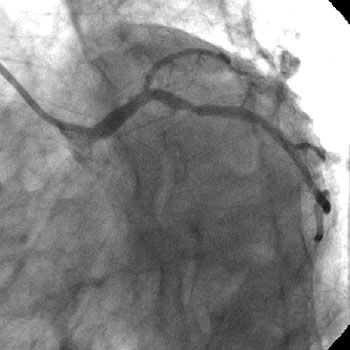

The left system was engaged with XB 3.5 guiding catheter through the femoral route. With the help of a 1.1x1.5mm CTO balloon, we directed a Shinobi guidewire towards the ostial LAD lesion (Figure 4). After making sure that the guidewire was pointing towards the CTO with its tip at the CTO lesion, we used the torquer to gently twirl the guidewire without forcing or overly manipulating it and allowed the guidewire to find its own way through the CTO by patiently twirling it at the lesion site. Within a few minutes, the guidewire jumped through the CTO lesion (Figure 5) and then through the lesion with the help of the CTO balloon (Figure 6). The path was first confirmed by engaging the RCA from the radial approach and injecting dye into the RCA (Figure 7). The CTO was then predilated with a 2.0x30mm Sapphire balloon (Figure 8 and Figure 9) and stented it with a 3.0x36mm DES (Figure 10 and Figure 11). Later the RCA was engaged with a JR 3.5 guiding catheter. A Cougar guidewire crossed the RCA lesion that was directly stented with a 3.0x13mm BMS (Figure 12 and Figure 13).